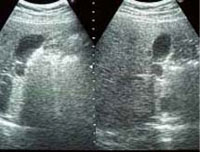

エコー写真

▼ 乳癌・乳腺症の早期発見・診断

▼ 肝臓・胆のう・すい臓の診断